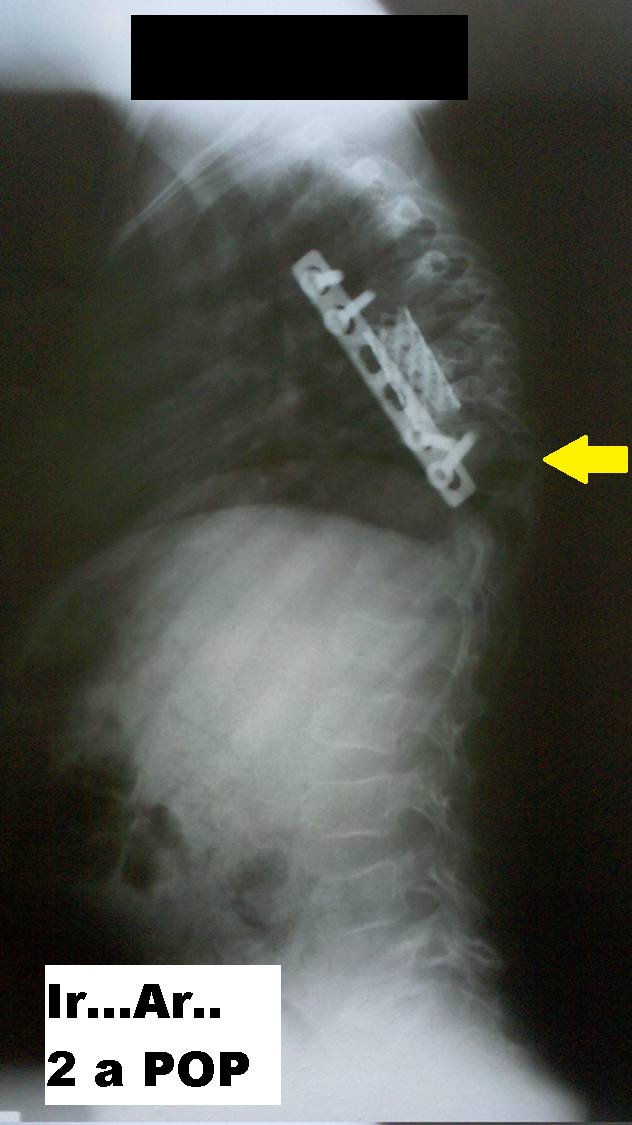

- Figura No 4a

- Figura No 4b

- Figura No 4c

- Figura 4 Texto